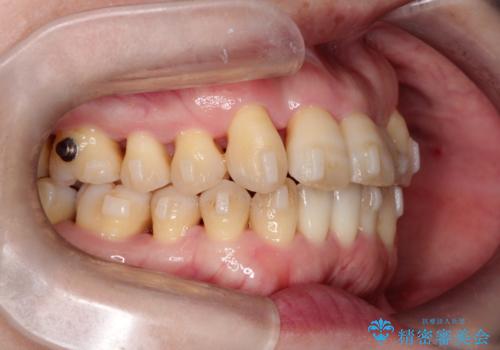

【インビザライン】ずれた前歯の噛み合わせをなおしたい

- 前歯の噛み合わせが悪いことを主訴に来院されました。

歯周病も併発していたため、歯牙への負担が少なくなるように治療計画をたて、インビザラインにて治療を完了しました。

矯正開始前に半年間、歯周治療を行ってからインビザラインを装着しています。